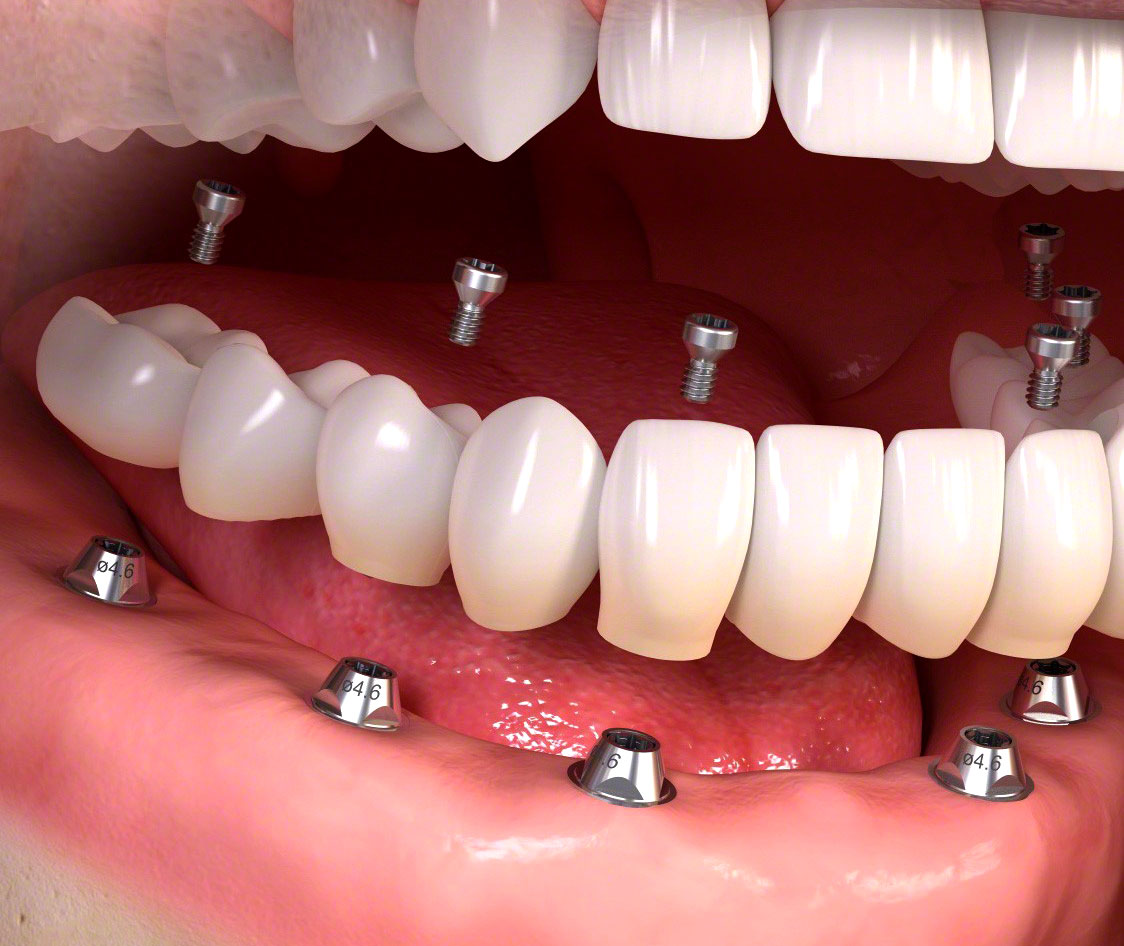

Клініка UkrDentClub пропонує безпечний метод класичної двоетапної імплантації. На першому етапі хірург-імплантолог вживляє до щелепної кістки титановий штифт, ушиває м’які тканини, встановлює формувач ясен і заглушку. Потім імплант приживається протягом кількох місяців: від 2 до 6 залежно від клінічної картини та різновиду імплант-системи. На другому етапі, коли вже немає ризиків первинного відторгнення, виконується протезування. Це оптимальний спосіб відновлення зубів, якщо пацієнт має медичні протипоказання, фінансовий чи психологічний бар’єр до одноетапної імплантації.

На другому етапі відбувається:

- Процедура встановлення абатмента – перехідника між імплантом і коронкою.